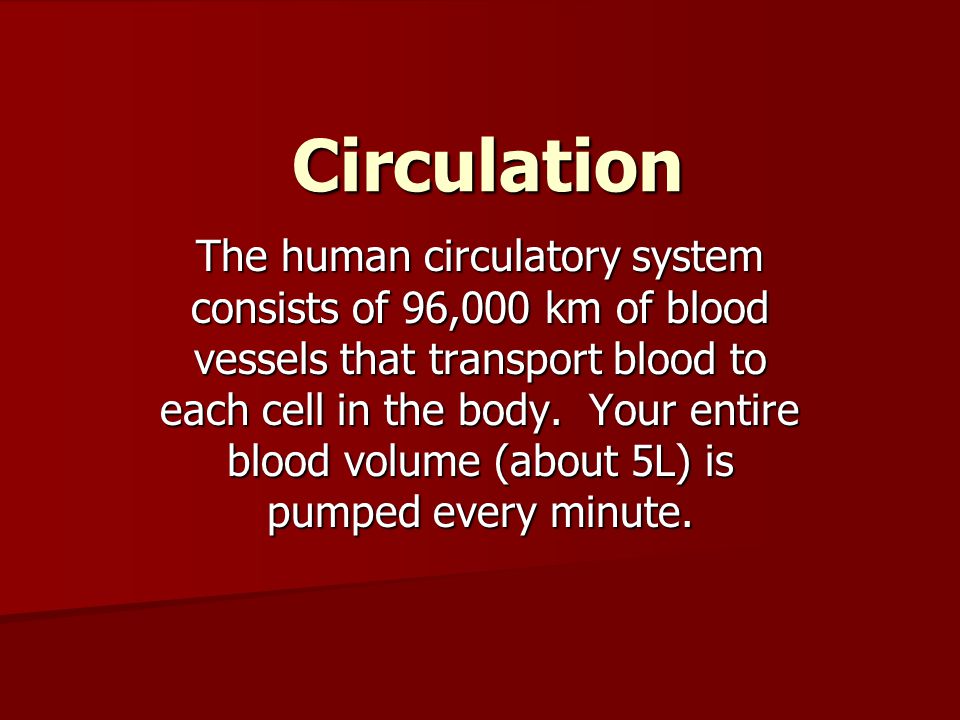

6. The Circulatory System (human)

- Components of blood and their functions (Red blood cell, white blood cell, platelets and plasma (blood groups)

- Blood vessels (arteries, veins, and capillaries)

- The heart (structure and function)